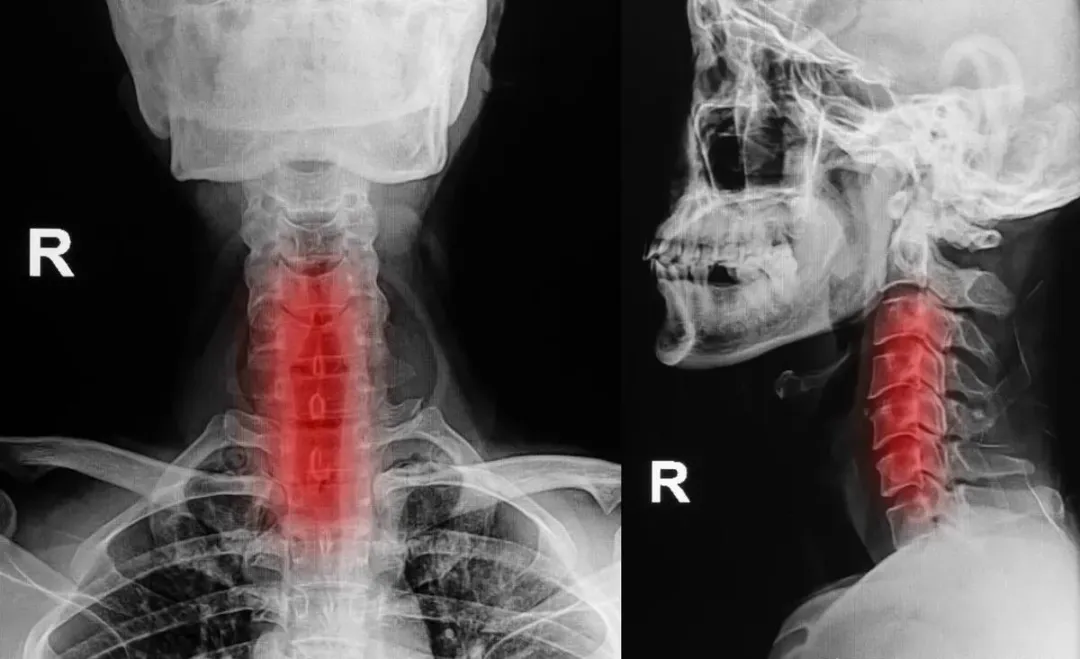

脊椎退行性改变是脊椎结构随年龄增长或长期劳损发生的慢性退变过程,主要涉及椎间盘、椎体、小关节及周围韧带等结构。(简单来说就是机体功能衰退,器官或骨头老化出现的一种改变)。

这种退变分为正常变化和病变,其中病变是可以导致疼痛、神经压迫和活动受限,常见于颈椎、腰椎等负重较大的脊柱阶段(胸椎椎间盘髓核在中央,故稳定性较好)。